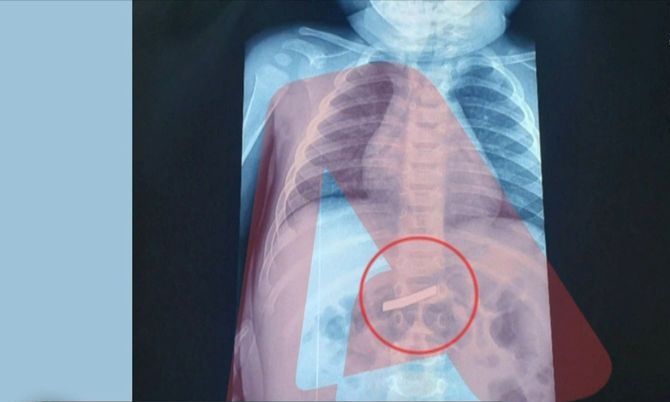

Η ακτινογραφία έδειξε ότι όντως υπήρχε ένα ξυραφάκι στο σώμα του παιδιού - Υποβλήθηκε άμεσα σε χειρουργική επέμβαση Περισσότερα...